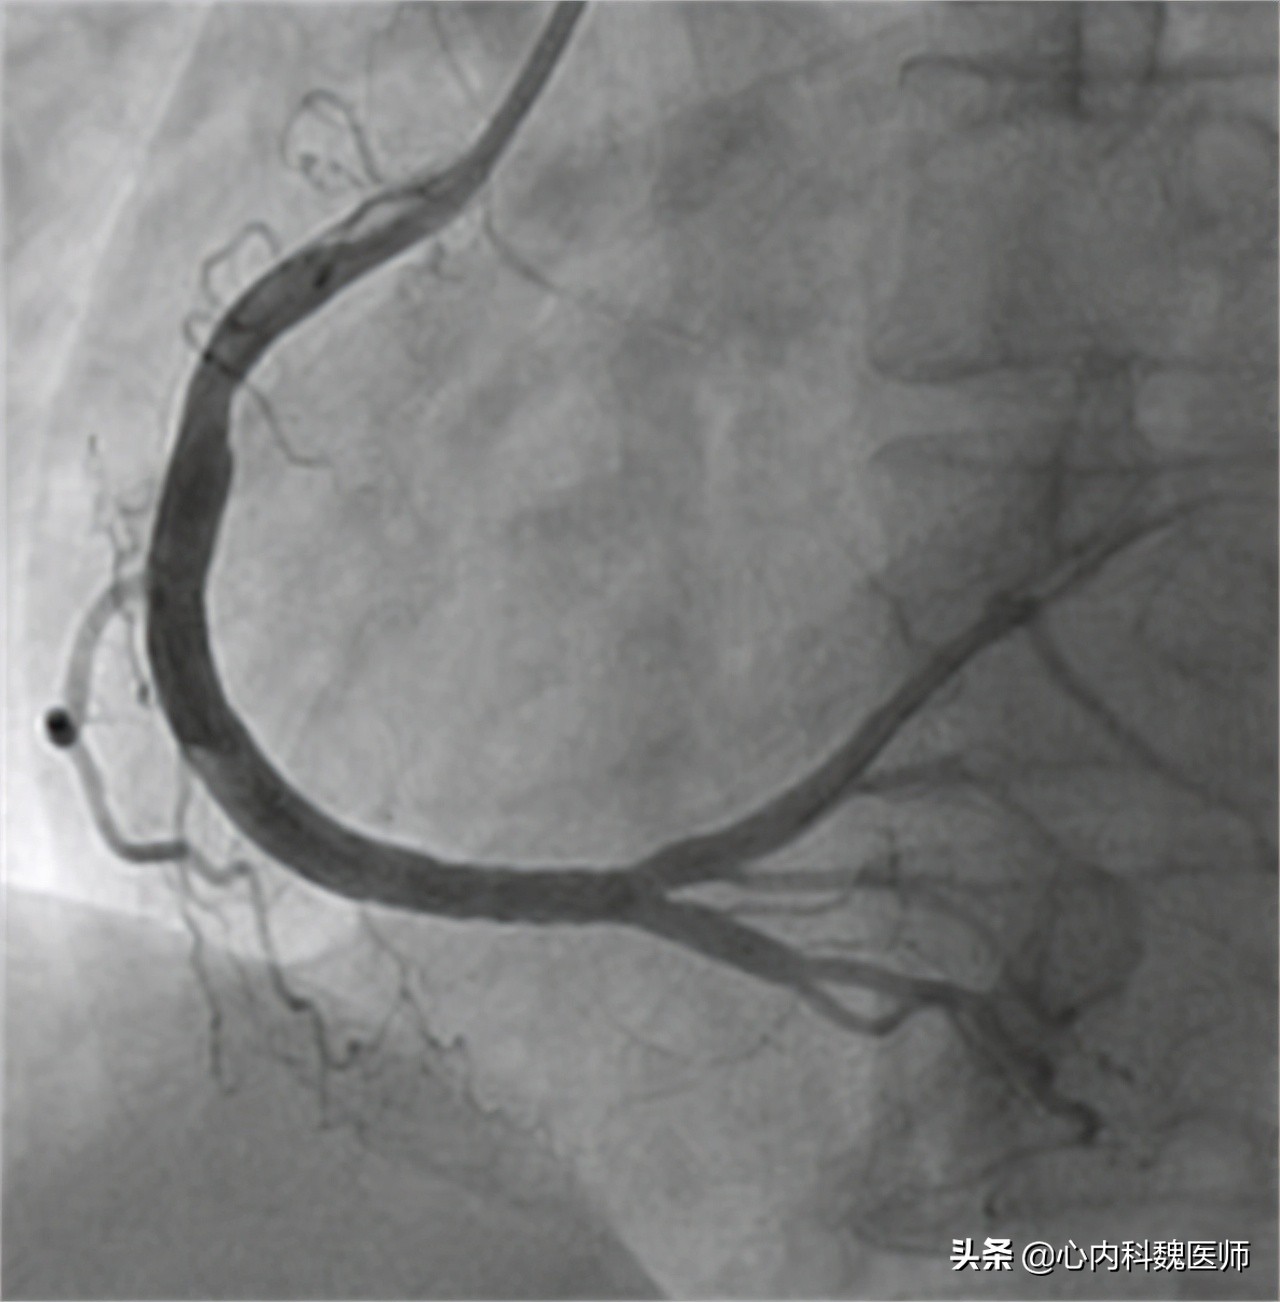

高大爷向医生说明了自己8年的冠心病史和一直没有服用药物的状态,医生害怕高大爷的病情进一步加重,于是做了简单的查体后就安排了高大爷住院进行心脏冠脉造影的检查。检查结果出来后,医生十分奇怪高大爷的情况。

医生:“大爷,根据您造影的情况,冠状动脉堵塞还不到 百分之二十五 ,远够不上冠心病的标准啊,到底是谁告诉您有冠心病的?”

患者体温36.5℃、血压130/90、身高168cm、体重68kg。心电图提示心脏存在明显早搏现象。心脏造影显示主动脉堵塞百分之二十三,排除冠心病。

医生:“冠心病的最佳诊断方法就是做 冠状动脉造影 ,因为这是最直观观察冠状动脉情况的检查。但是鉴于这种检查对患者会造成一定的创伤,所以我们只有在高度怀疑患者有冠心病的时候才会考虑。”

医生:“还有一种检查被叫做 冠脉CT ,这种检查虽然没有造影那么直观,但是可以作为辅助诊断冠心病的检查,当检查结果提示患者的冠状动脉重度狭窄时,大概率就是冠心病的症状,如果需要进一步确诊可以再考虑冠状动脉造影,检查具体堵塞的位置。”